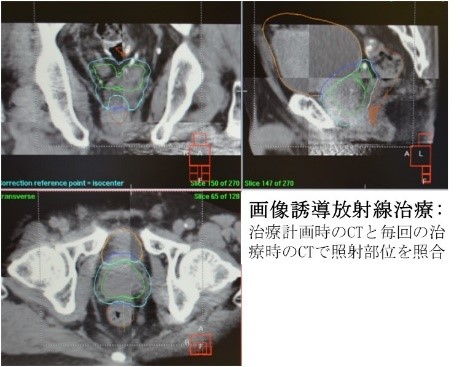

- 画像誘導放射線治療(IGRT; Image Guided Radiation Therapy))

画像誘導放射線治療(IGRT; Image Guided Radiation Therapy)

放射線治療では可能な限り正しい部位に照射することが重要です。高精度放射線治療である定位放射線照射(STI)や強度変調放射線治療(IMRT, VMAT)で狙い撃ちをしても、実際の放射線治療時の照射位置がずれてしまっては、治療効果が保持されないだけでなく副作用も増加してしまいます。当科では、放射線治療装置に付属しているCTを用いて治療前に腫瘍の位置がわかる画像を取得し、照射部位と腫瘍位置のズレがないかどうかを確認した上で照射を開始することで、より正確な放射線治療を実践しています。定位放射線照射(STI)や強度変調放射線治療(IMRT, VMAT)に画像誘導放射線治療(IGRT)を併用することで、高い治療効果で軽い副作用を目指した放射線治療を行っています。